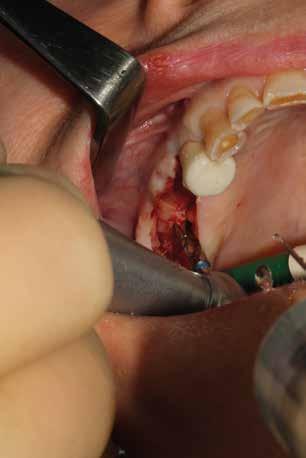

Esempio chirurgico di accesso tra 2 elementi dentari con conformazione della cresta alveolare ampia. Incisione del lembo in cre sta senza scarichi laterali con sollevamento di 2 lembi, palatale e vestibolare; si può notare come quest’ultimo non si estenda oltre

Estrazione di 3 elementi dentari complicata da frattura coronale di 2.4 e presenza di 2 corone protesiche unite su denti pluriradicolati. L’approccio deve prevedere la rimozione delle corone protesiche e la separazione delle radici, semplificando le manovre di estrazione e consentendo di risparmiare i tessuti molli pericoronali e prevenire la frattura

Il rispetto dei tessuti molli consente di ridurre i tempi di guarigione, sebbene a siti più ampi corrisponda un tempo di ripristino o maggiore. Il mantenimento delle corticali vestibolari, palatine e l’assenza di alveolite post-estrattiva riducono l’atrofia ossea.

Un ridotto scollamento dei tessuti molli riduce edema e dolore post operatorio, mentre la preparazione del sito implantare a bassi giri con irrigazione limita il trauma del tessuto osseo.

Una incisione lineare netta si estende coinvolgendo minimamente il dente mesiale e maggiormente in direzione distale, consente di evitare l’esecuzione di incisioni di scarico che provocano una interruzione della vascolarizzazione maggiore, senza ridurre la visibilità del campo operatorio.

La microvibrazione degli inserti ultrasonici non presenta la tendenza allo scivolamento tipica delle frese rotanti consentendo di mantenere con maggiore semplicità e precisione l’orientamento del tunnel implantare, soprattutto quando si prepara all’interno dei un alveolo post-estrattivo agendo su una superficie liscia e inclinata. Nelle immagini è possibile vedere una serie di situazioni in cui

Una pulizia approfondita e delicata può essere effettuata con il piezo-clean anche su piani ossei coinvolti dalla chirurgia resettiva. Lo strumento crea una zona circoscritta di applicazione di ultrasuoni amplificando l’azione di detersione dei residui di tessuto necrotico, di microorganismi patogeni e di vasocostrizione, che migliora la visibilità del sito.